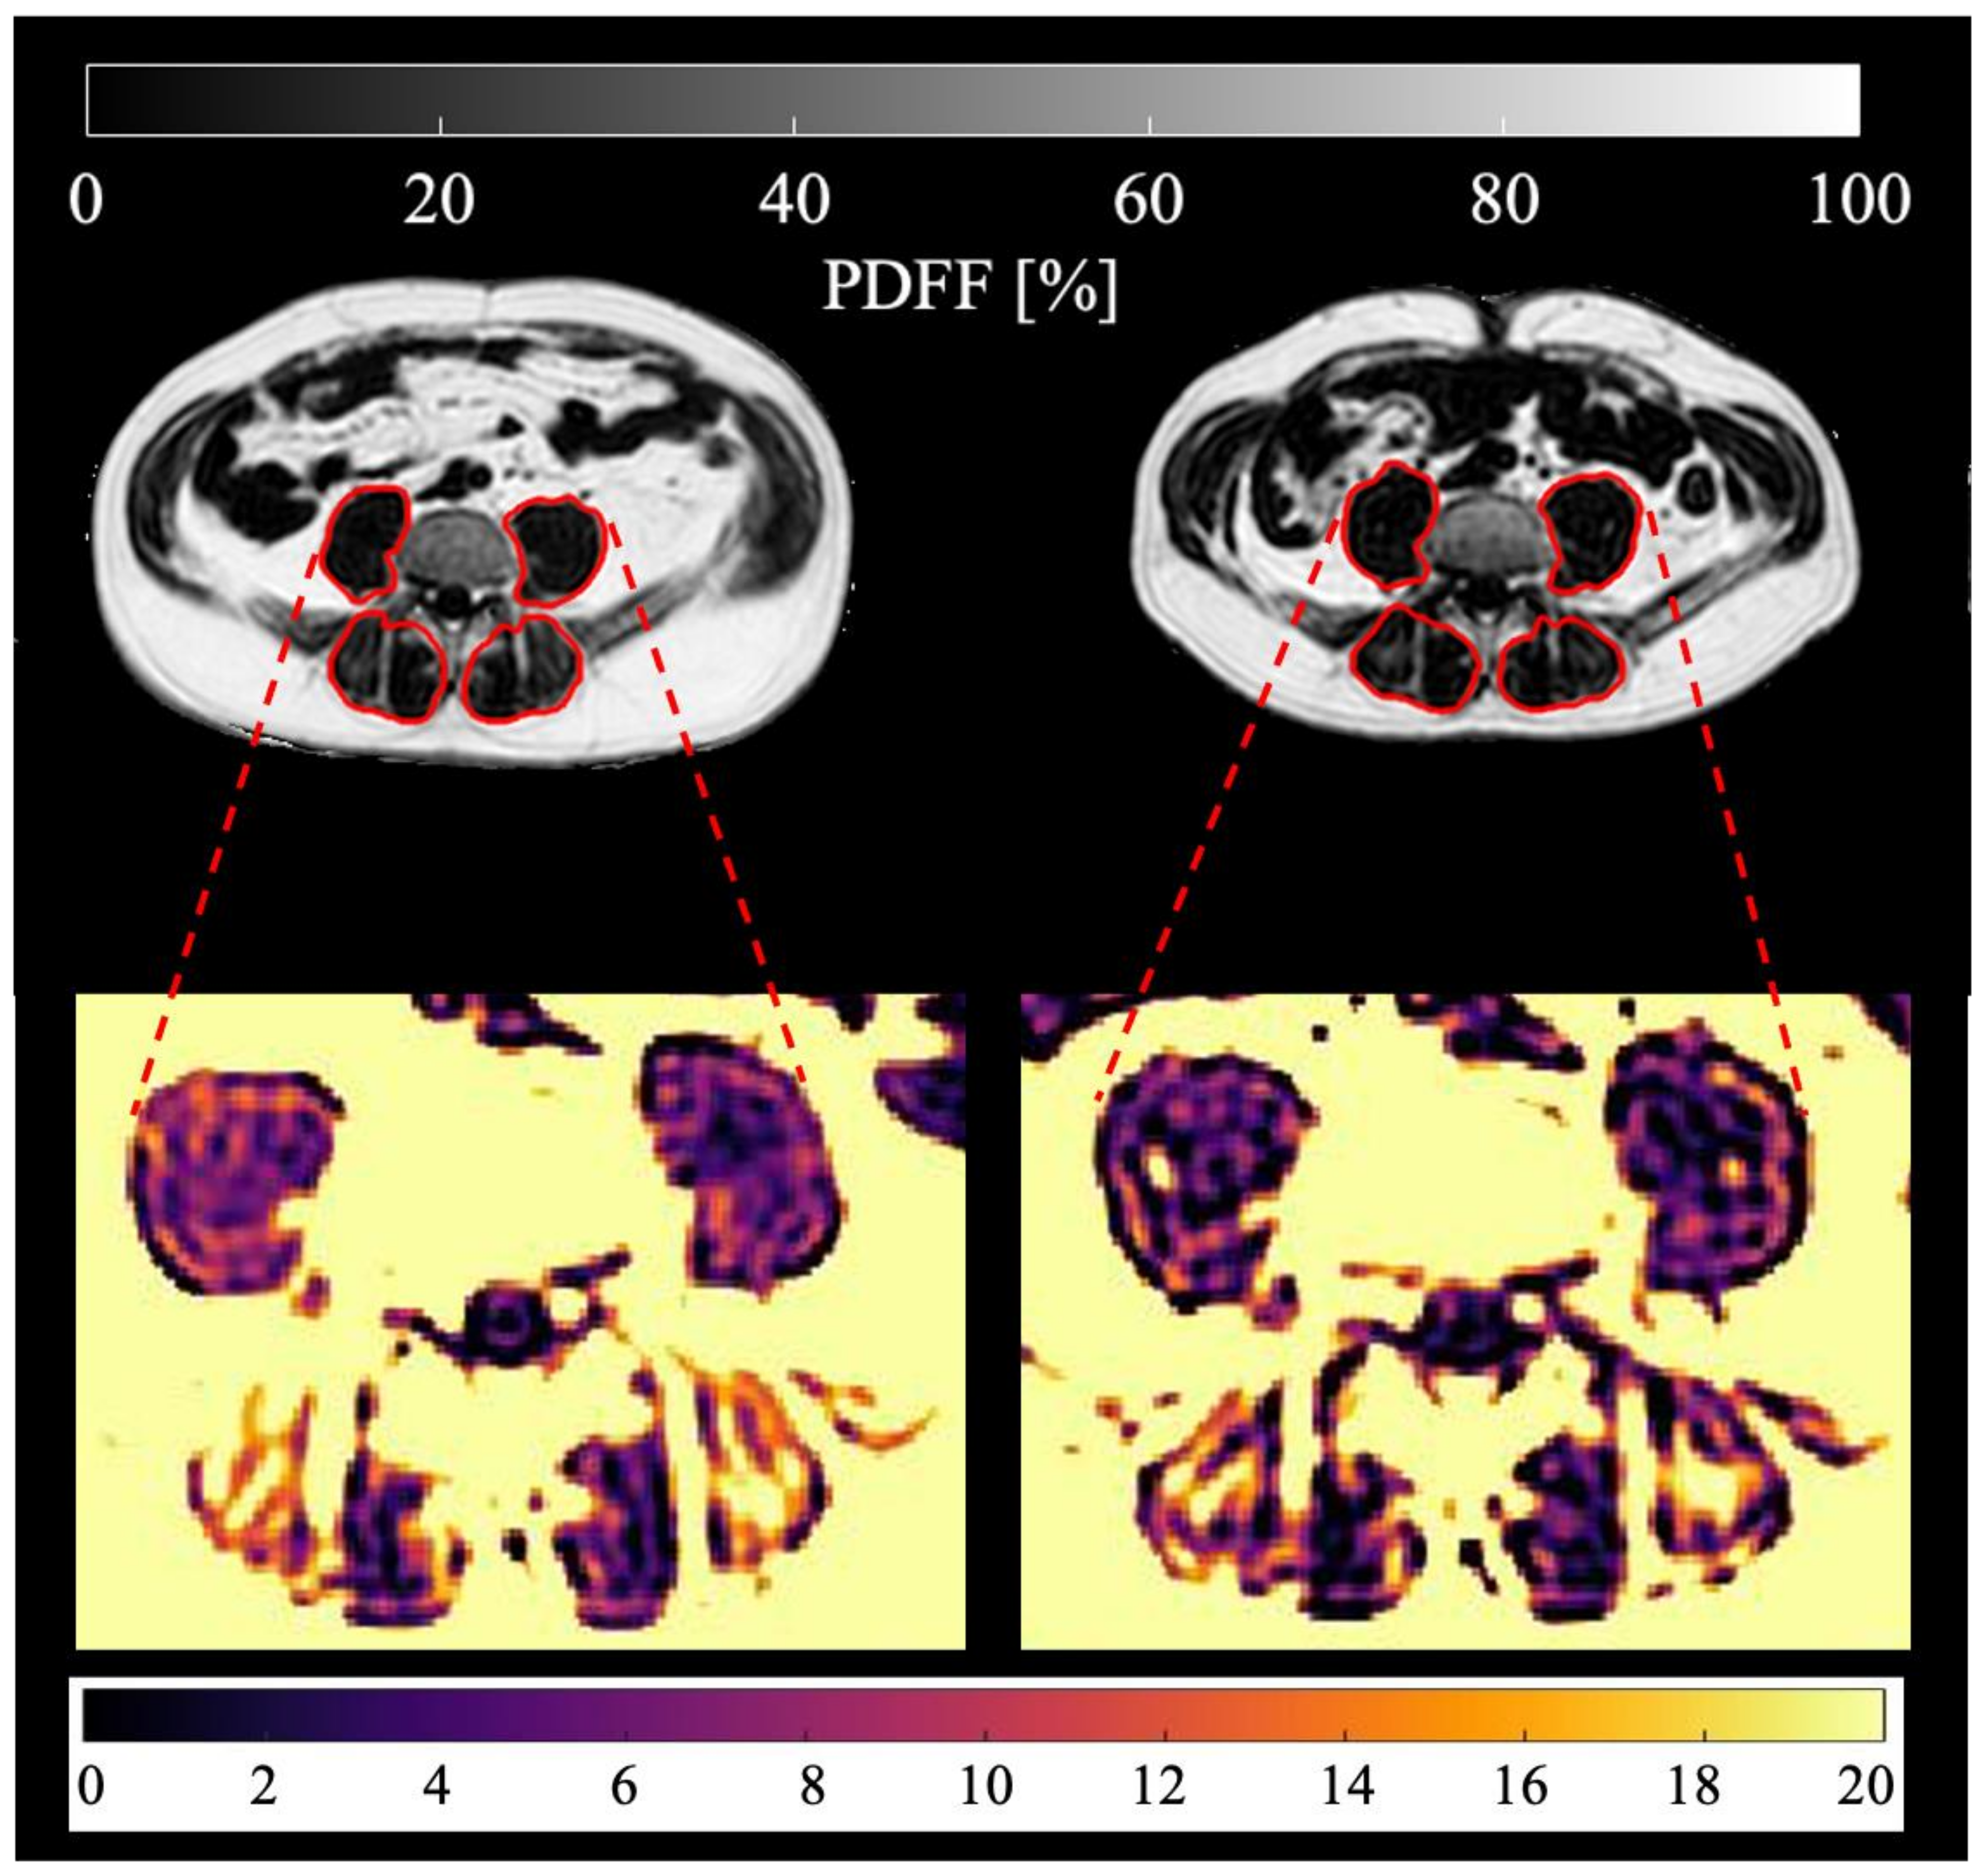

Figure 3.

Visualization of absolute maximum change of M. psoas PDFF on the left, relative maximum change of muscle volume, contractile tissue volume and fat volume per proximal, middle and distal muscle section on the right. Statistical significance of change tested with one-sample t-test (compared to no change with test value = 0), △= <0.05, ▲= <0.01. No statistical significance of change differing between muscle sections (tested with one-way ANOVA analysis) was found.

Figure 4.

Visualization of absolute maximum change of M. erector spinae PDFF on the left, relative maximum change of muscle volume, contractile tissue volume and fat volume per proximal, middle and distal muscle section on the right. Statistical significance of change tested with one-sample t-test (compared to no change with test value = 0), △= <0.05, ▲= <0.01. Statistical significance of change differing between muscle sections tested with one-way ANOVA analysis, * = <0.05, ** = <0.01.

No statistically significant absolute change in PDFF for psoas and erector spinae muscle was observed in this study.